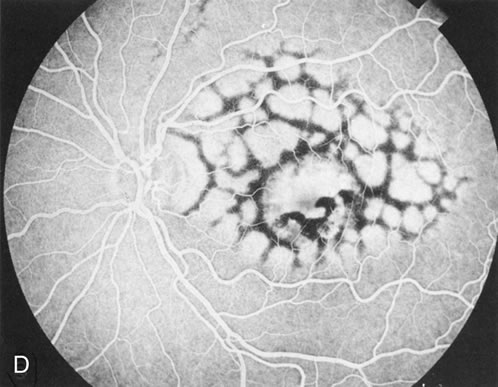

DOMINANT DRUSEN OF BRUCH'S MEMBRANE

There is no clear agreement as to what constitutes dominantly inherited drusen and what constitutes age-related degenerative drusen. There is a distinct group of younger individuals with bilateral, symmetric, uniformly small, round, discrete, yellow and white drusen. Histopathology demonstrates a nodular thickening of the RPE basement membrane, and these drusen have therefore been referred to as basal laminar, or cuticular, drusen.24

FA shows a characteristic pinpoint area of transmission hyperfluorescence corresponding to the drusen and reveals many more than are appreciated clinically (Fig. 12). Secondary changes such as pigment atrophy and dispersion, exudative and nonexudative detachments, and occasionally a neovascular membrane, will be revealed by FA (Fig. 12E).

Fig. 12. Dominant drusen of Bruch's membrane. The drusen appear as yellowish-white “blisters” predominantly in the temporal posterior pole (A). The angiogram shows many pinpoint areas of transmission hyperfluorescence typical of drusen, some of which have coalesced to form broader areas of hyperfluorescence (B). These drusen occasionally result in ingrowth of a choroidal neovascular membrane, such as occurred in this case over a 5-year period (C–E).